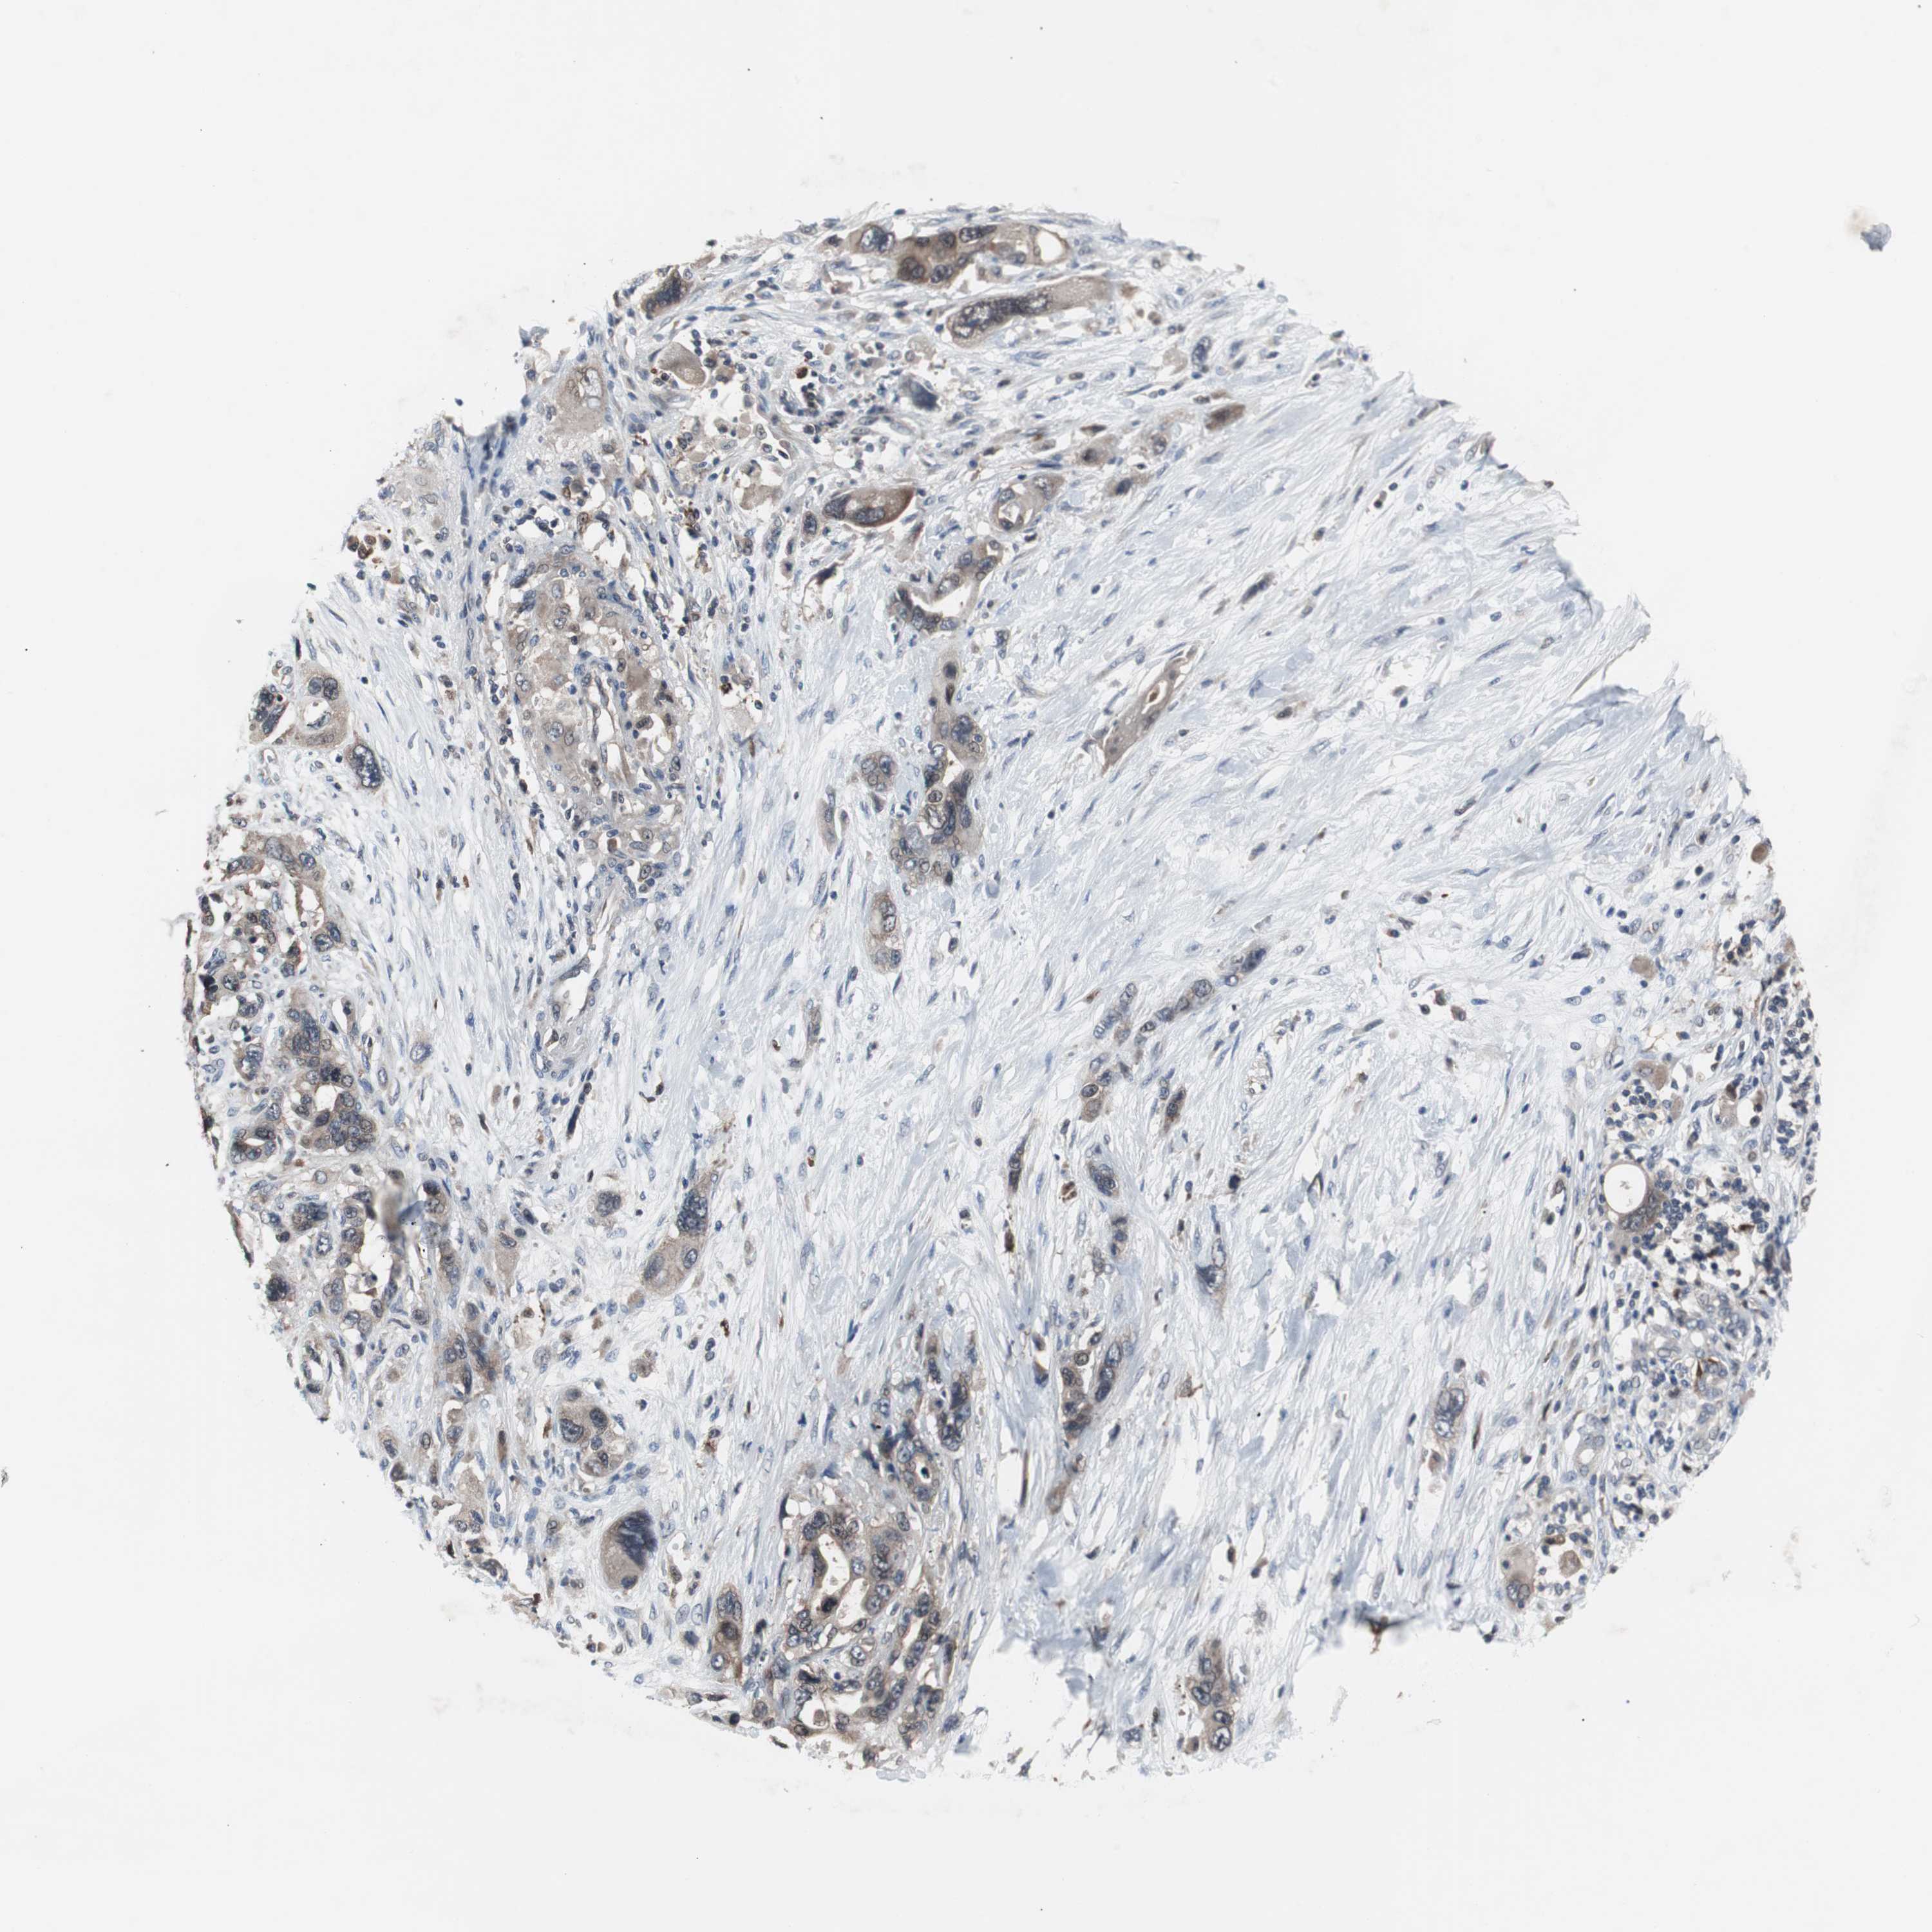

PANCREATIC CANCER - Protein expressioni

A mouse-over function shows sample information and annotation data. Click on an image to view it in a full screen mode. Samples can be filtered based on level of antibody staining by selecting one or several of the following categories: high, medium, low and not detected. The assay and annotation is described here.

Note that samples used for immunohistochemistry by the Human Protein Atlas do not correspond to samples in the TCGA dataset.

Antibody stainingi

Antibody staining in the annotated cell types in the current human tissue is reported as not detected, low, medium, or high, based on conventional immunohistochemistry profiling in selected tissues. This score is based on the combination of the staining intensity and fraction of stained cells.

Each image is clickable and will lead to virtual microscopy that enables deeper exploration of all samples and also displays staining intensity scores, fraction scores and subcellular localization as well as patient and tissue information for each sample.

Antibody HPA003565

Antibody CAB005312

Staining

High

Medium

Low

Not detected

Intensity

Strong

Moderate

Weak

Negative

Quantity

>75%

75%-25%

<25%

None

Location

Nuclear

Cytoplasmic/membranous

Cytoplasmic/membranous,nuclear

Adenocarcinoma, NOS

Adenocarcinoma, metastatic, NOS